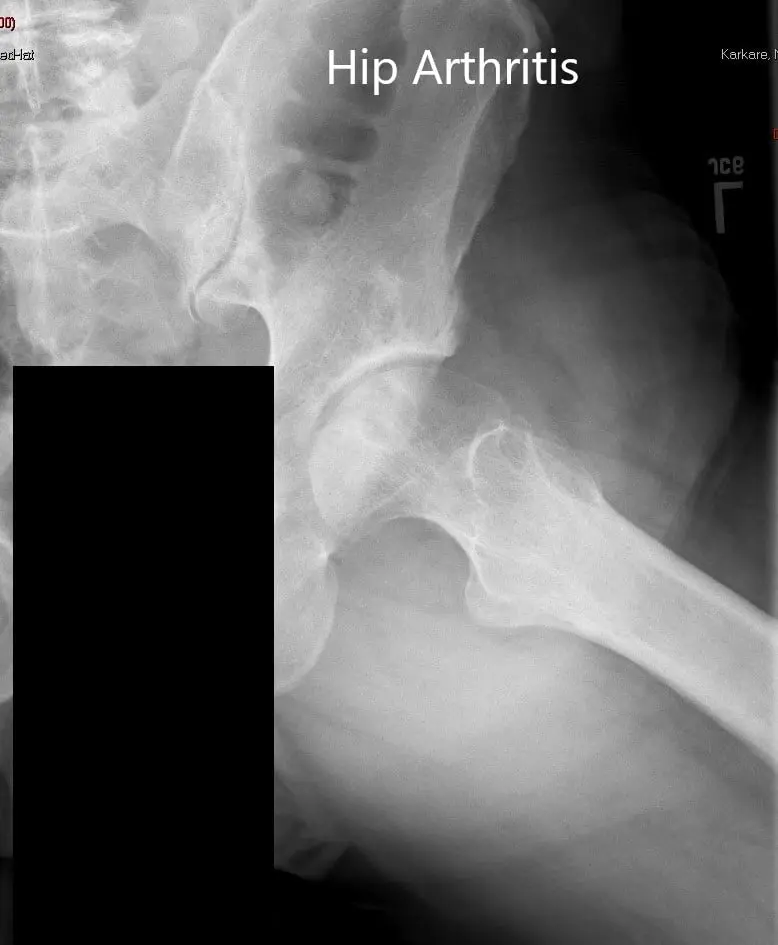

Las imágenes revelaron osteoartritis severa en la cadera izquierda con quistes subcondrales, esclerosis y osteófitos. El acetábulo izquierdo era poco profundo con el cuello femoral izquierdo acortado.

Radiografía preoperatoria de la pelvis que muestra una vista AP de la pelvis con ambas caderas.

Radiografía preoperatoria de la cadera izquierda en vistas AP y laterales con patas de rana.